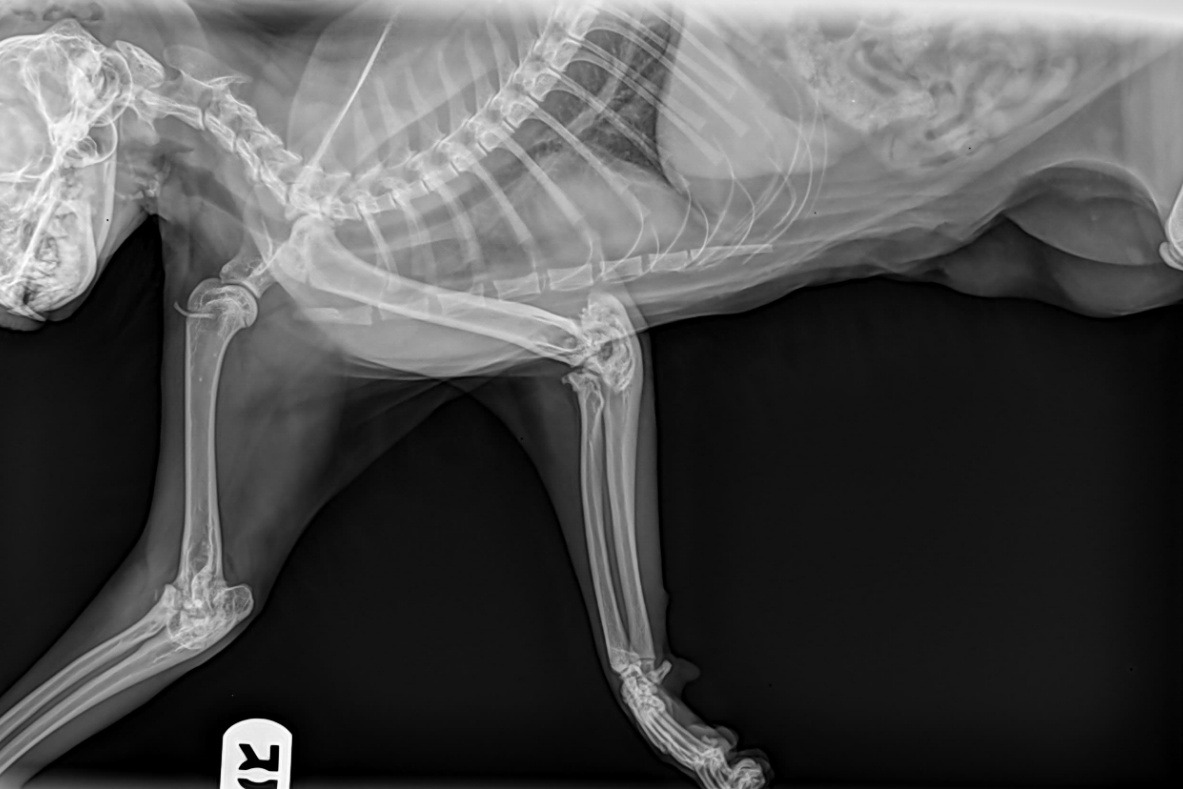

An x-ray was taken at the ER as well as medication to stop the pain, and turns out her elbow joints are completely malformed.

Below is the report that was concluded from it.